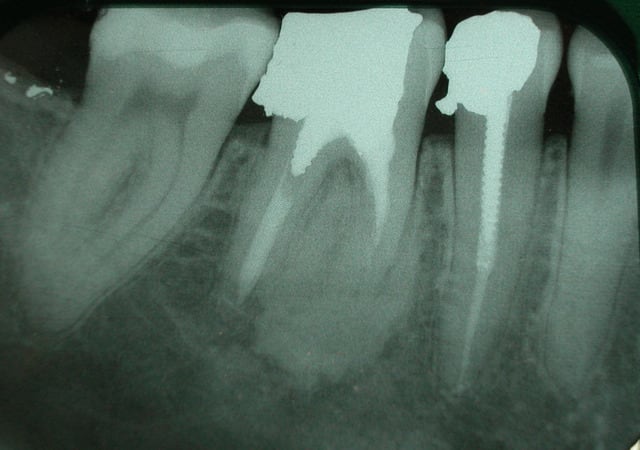

qu'est que cela peut il etre?

dent asymptomatique.

Normal mon chou, rien à faire lésion cemento-osseuse très difficile à classer même pour l'oms

tu peux écarter les fibromes cemento-ossifiant (il manque le halo radio clair périphérique) e n'est pas non plus une dysplasie fibreuse il n'y apas de déplacement de structure dentaire tu peux t'orienter vers une dysplasie céménto-osseuse péri apicale à forme dense quel age? Femme?

je ne suis pas endo, mais en temps qu'osseuphile je ne rettt pas pas d'inflammation sup dans ce flou ossifiant et les images en distal de la 7 c'est là depuis longtemps ou c'est de l'amalgame tout frais, fais ta couronne en expliquant la présence de cette image ostéocondensante à la patiente , femme 3 décade correspond bien avec une dysplasie cemento-osseuse terme anapath qui veut dire on s’en fout il ya des cellules cementaire et osseuses en structure malformative résultant d'une anomalie du développement d'un tissu .

pour le bout d'amalgame figée en distale de 47, je ne sais pas depuis quand il est là car c la première fois que je vois la patiente.

dernière interrogation, ce phenomene est il associé à une resorption radiculaire?(qui pourrait comprometre la durée de vie de la dent?)

tres lentement evolutif certe!